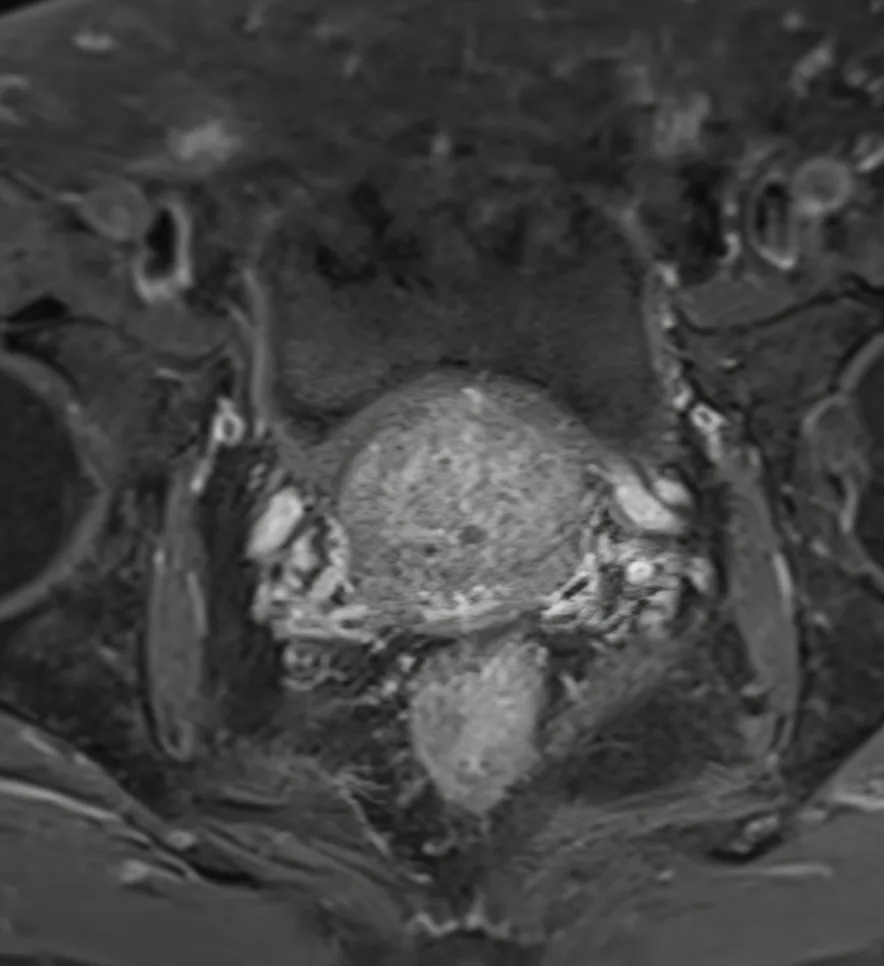

- MRI disease correlated with PSA & stabilised or shrunk in 91%